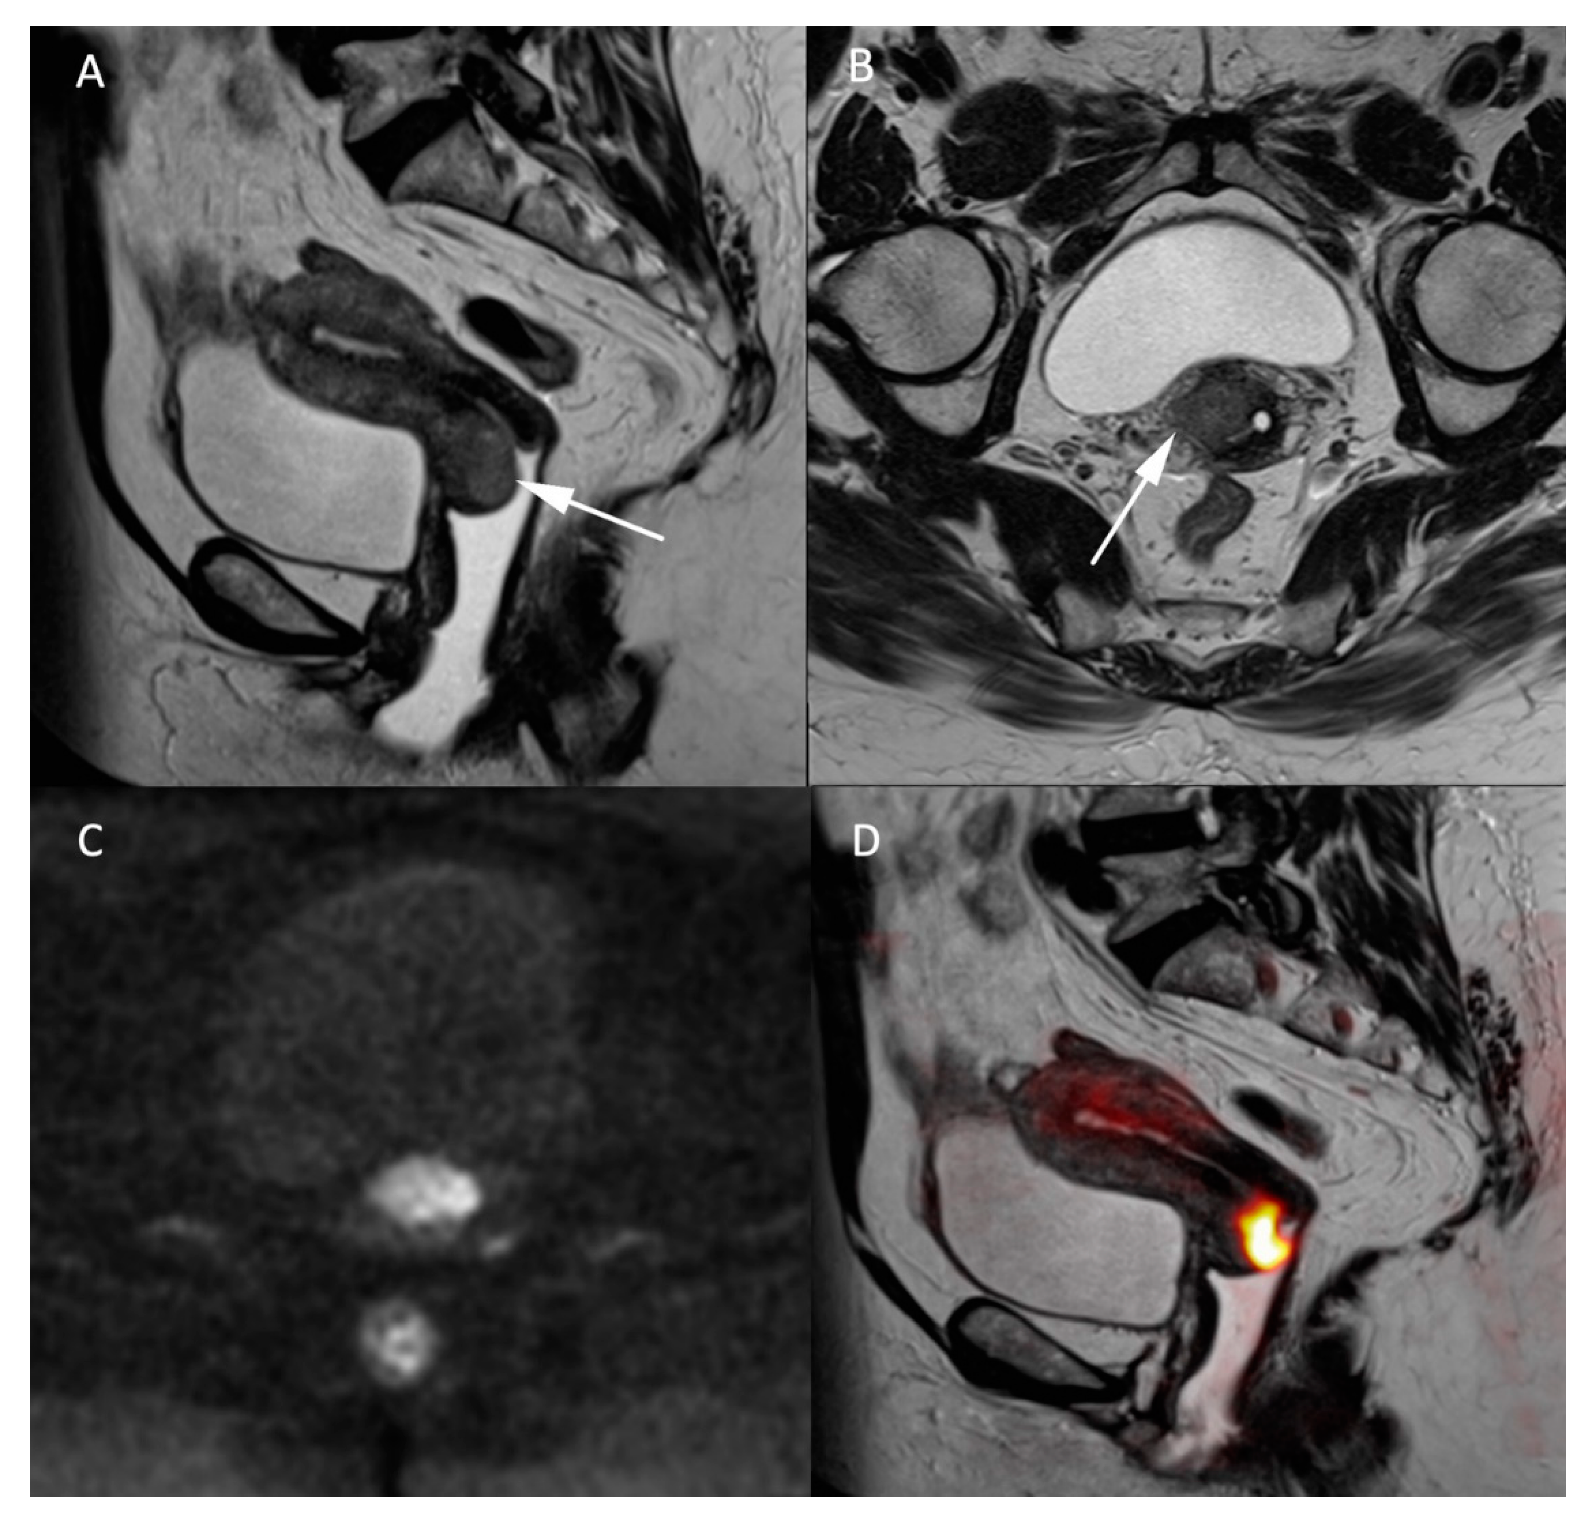

Figure 2.

MR images of a 66-year-old woman with a known cervical carcinoma. (A) Sagittal T2W image; (B) axial T2W image perpendicular to the cervical axis. Cervical cancer and its extension appearing as low-contrasted T2W area (arrow) through the normal stroma and the right parametrium, (C) high b-value (b = 1000 s/mm2) and (D) fusion images between T2W and high b-value sequences for better evaluation of the carcinoma’s extension.